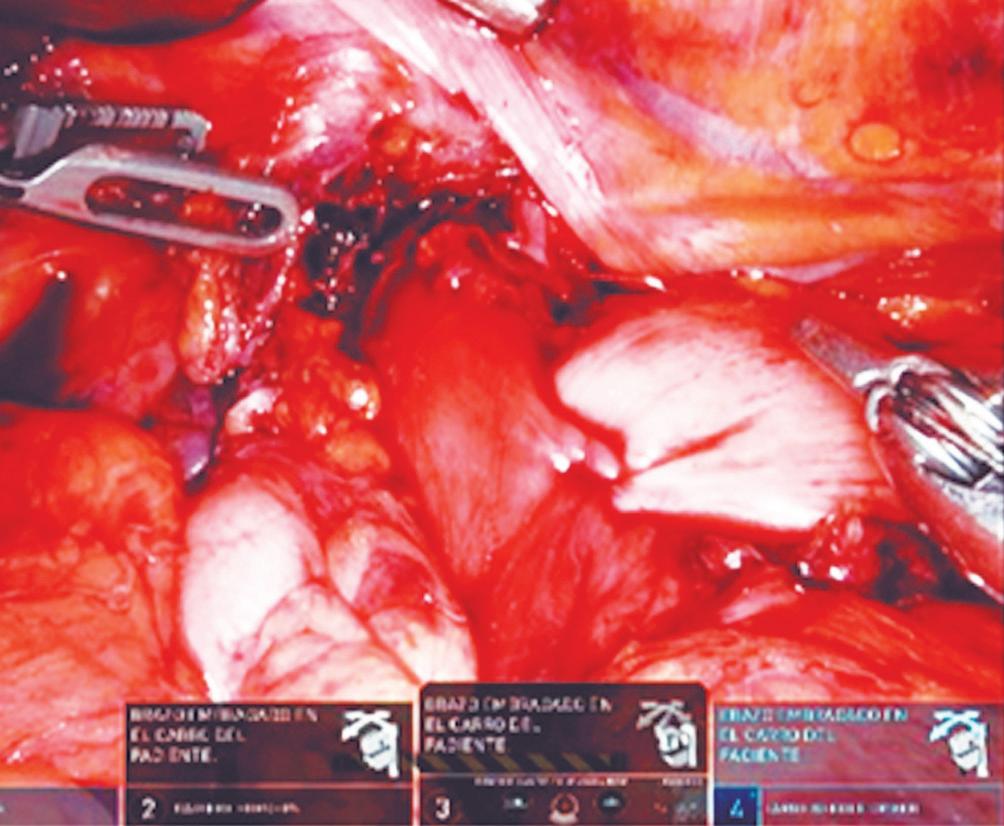

Evaluación de un paciente con dolor epigástrico y hallazgos sincrónicos infrecuentes

Roy López Grove, Daniela Soloaga, Juan Carlos Spina

Roy López Grove, Daniela Soloaga, Juan Carlos Spina 398